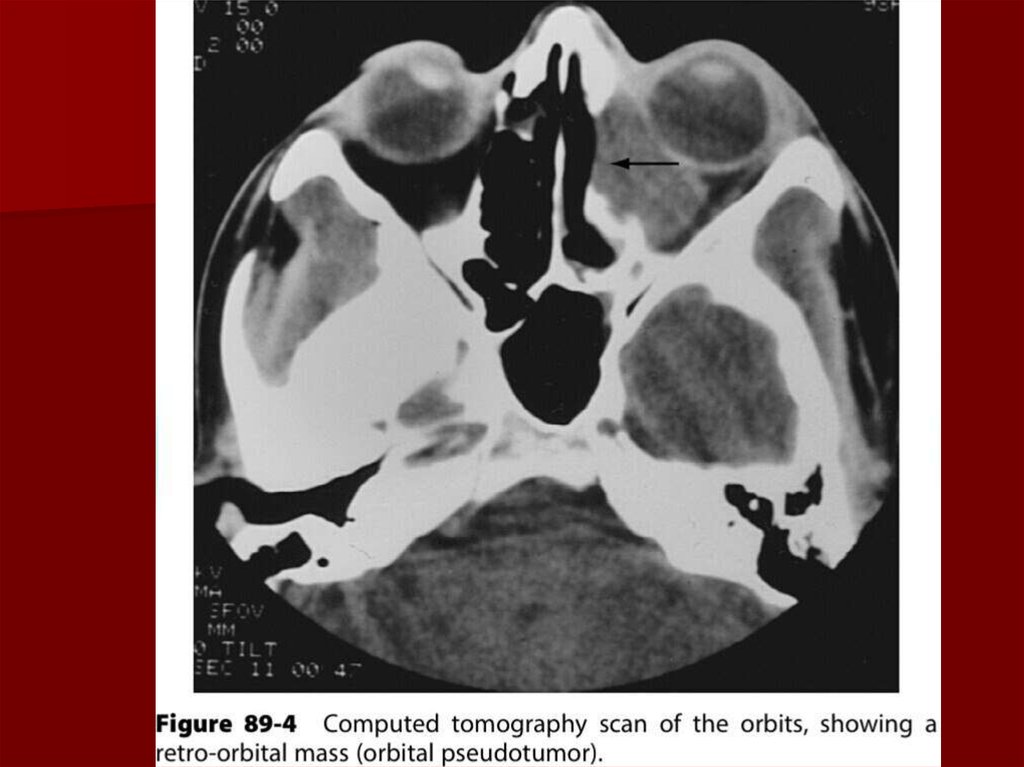

39. Диагностика